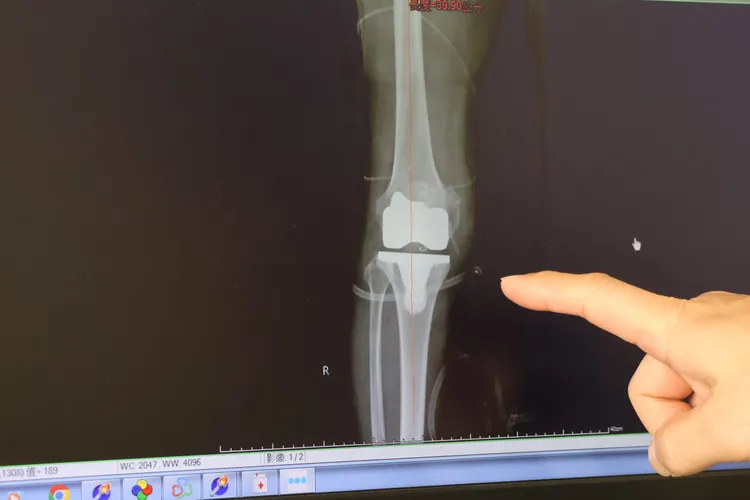

患者膝蓋退化,合併內翻變形15度。院方提供

台中大甲李綜合醫院副院長、骨科主治醫師王芳英說,這位阿公在手術前行走路自如,後來右邊膝蓋才痛到無法走路,最後要靠輔助器,經過檢查,發現退化性關節炎已經屬於第四期,軟骨已經磨穿、硬骨也變形,合併內翻變形15度,跨科醫師評估患者身體況狀良好,決定進行換上人工關節,同時做內側韌帶的放鬆手術。手術時間大約2個小時,術後矯正後腳已變直,隔天能下床行走,兩天後能爬樓梯。